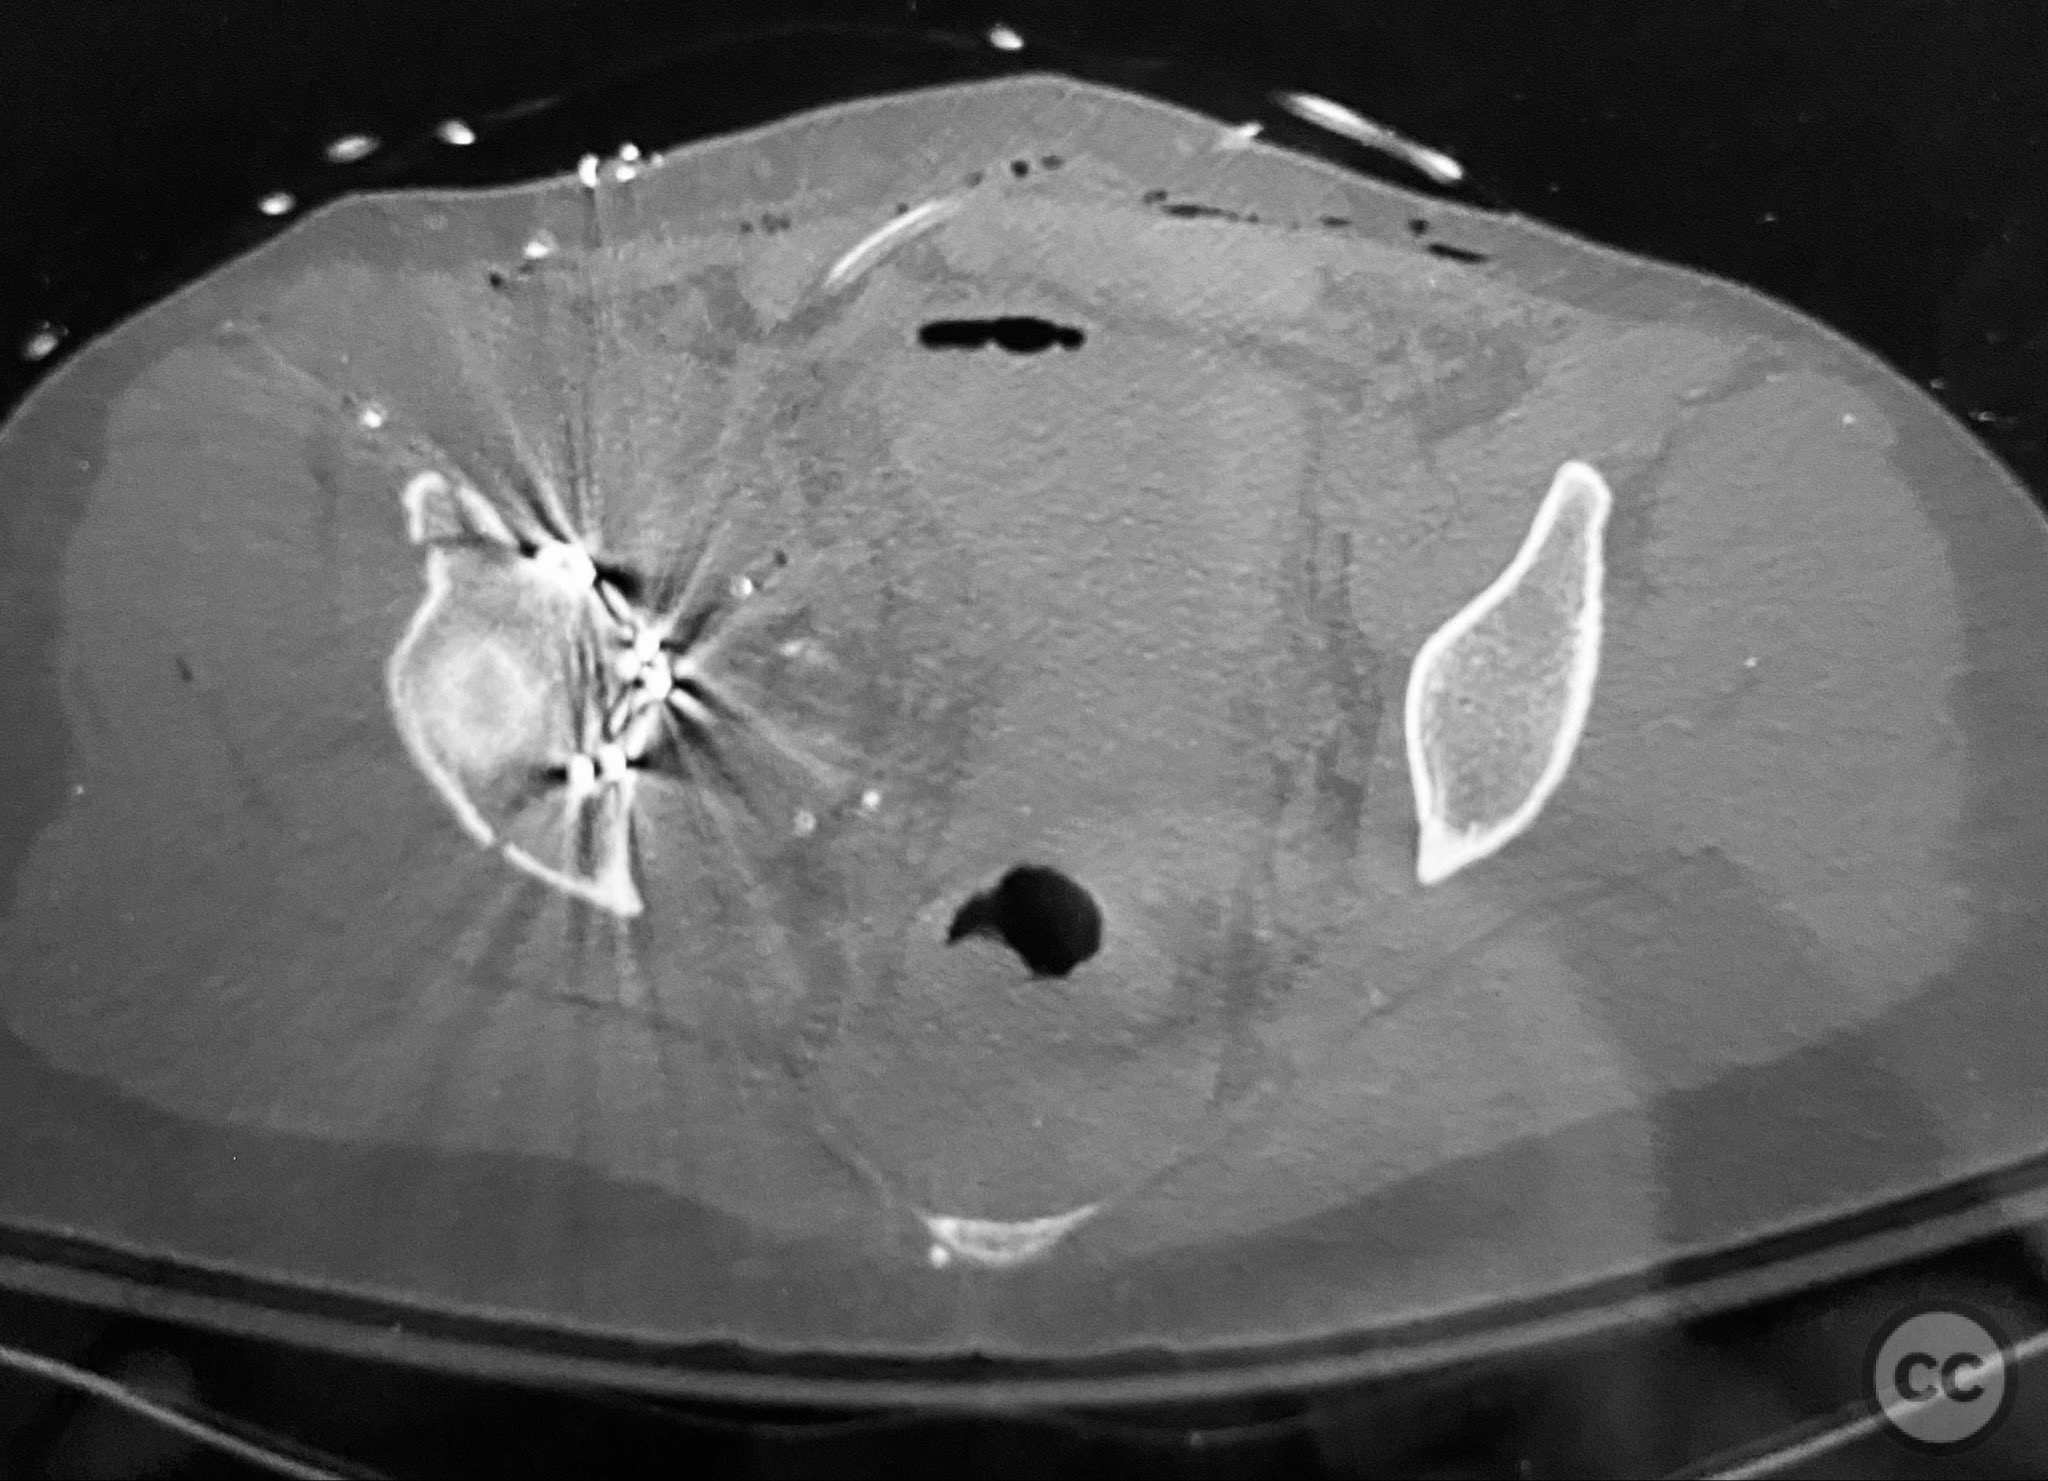

Clinical and radiological findings:  The patient sustained a complex both column acetabular fracture, AO/OTA 62C1, characterized by several large columnar fragments, an independent anterior inferior iliac spine (AIIS) fragment, a notable dome fragment predominantly attached to the posterior wall (PW) fragment, and a distinct parasymphyseal injury zone. Initial application of a pelvic binder resulted in increased displacement of the fracture fragments. Preoperative imaging, including surface renderings and multiplanar CT, demonstrated the independent AIIS fragment, detailed cortical surfaces, and the orientation of fracture planes. The majority of the acetabular dome was associated with the PW fragment, a critical detail for surgical planning and reduction.

The anterior column fragment was reduced first under direct visualization and held with a 6-hole plate and lag screw. The 12-hole intrapelvic plate was then contoured and applied along the pelvic brim to reinforce the reduction. The posterior column and posterior wall fragments, including the dome component, were stabilized with lag screws placed through safe osseous corridors under fluoroscopic guidance. The independent AIIS fragment was addressed during the exposure and incorporated into the reduction construct. The parasymphyseal injury zone was inspected for stability following fixation. Postoperative CT confirmed anatomical reduction and stable fixation of all fragments.

Orthopaedic implants used:   6-hole reconstruction plate, 12-hole intrapelvic plate, multiple lag screws